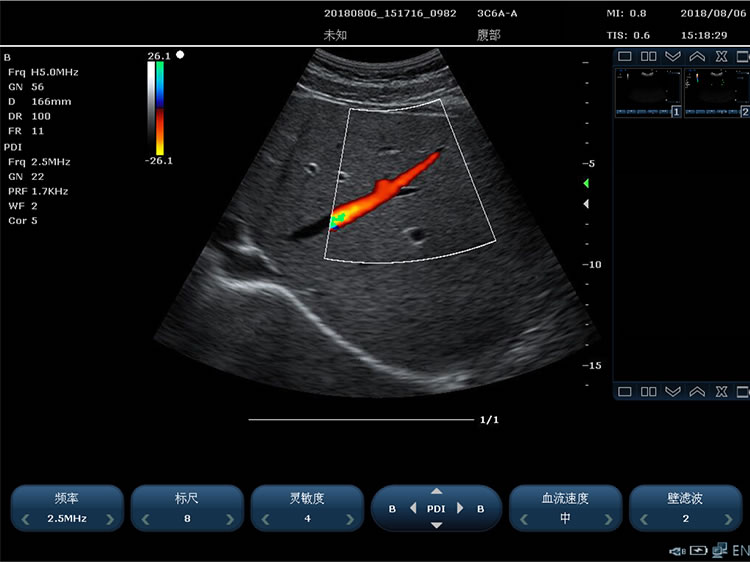

3)能量多普勒成像 4)PHI脉冲反相组织谐波成像+频率复合技术

1)成像模式包括:B 模式、2B模式、4B模式,M模式、Color(彩色多谱勒)模式、PDI(能量多普勒)模 式、PW 模式、CW 模式、解剖M、B+C+PW 三工、B+PDI+PW 三工、支持单窗口显示, 双窗口实时显示,四窗口显示

12.彩色多普勒技术要求:

1)多普勒增益连续可调 2)彩色增强功能

3)具备同屏左右双幅同时显示 B+COLOR 功能 4)彩色模式基线调节±15 级